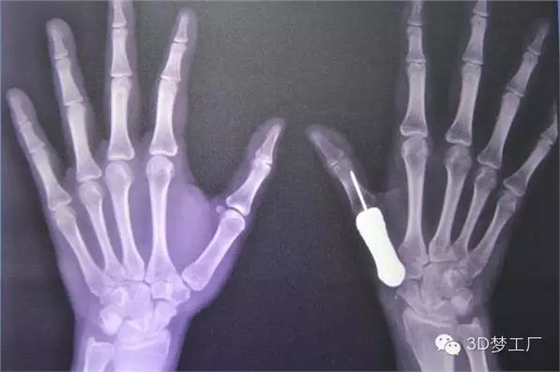

2016年1月26日,泰國曼谷Phramongkutklao醫(yī)院的醫(yī)生們宣布,他們成功用3D打印鈦金屬假體替換了一個拇指掌骨。這在世界上還是第一次。該醫(yī)院骨科主任ThipachartPunyaratabandhu博士在宣布這則消息的同時(shí)詳細(xì)介紹了他的團(tuán)隊(duì)是如何將一個3D打印的鈦金屬拇指指骨植入一位女性患者的手上,這位患者原來的指骨由于腫瘤的出現(xiàn)已經(jīng)惡化。

治療團(tuán)隊(duì)一開始對病人健康的左手拇指進(jìn)行掃描和拍攝X光片,然后用鏡像的方法渲染出她的右手拇指指骨原來應(yīng)有的樣子,并用樹脂材料3D打印出其模型,最后用一種醫(yī)用鈦金屬鑄造出來。整個制造過程總共只用了一個星期左右,但是Phramongkutklao醫(yī)院骨科的醫(yī)生團(tuán)隊(duì)為了研發(fā)這個3D打印拇指項(xiàng)目已經(jīng)耗費(fèi)了將近兩年時(shí)間。

據(jù)了解,手術(shù)治療是從去年6月份開始的,當(dāng)時(shí)醫(yī)生將惡化的骨頭從病人手里取出來,并等了一段日子以確保腫瘤不會復(fù)發(fā)。當(dāng)這一情況在9月下旬確認(rèn)之后,外科醫(yī)生繼續(xù)手術(shù),植入鈦金屬指骨并將其與最近的肌腱連結(jié)在一起。